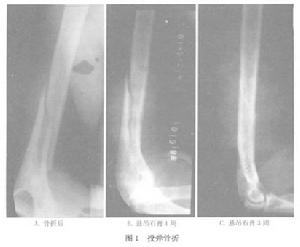

圖1病因

X線檢查,可顯示患肢骨折且多呈螺鏇形。

據作者百餘例的經驗,肱骨投彈骨折絕大部分不需要手術治療在懸吊石膏固定過程中,開始1周複查X線片可能骨折對位不滿意,此時不必急於改用手術治療,應仔細調整懸吊帶位置和長度,並強調患者做上臂肌肉等長收縮鍛鍊,在“肌肉夾板”作用下骨折對位大多可達到治療要求(圖1)。